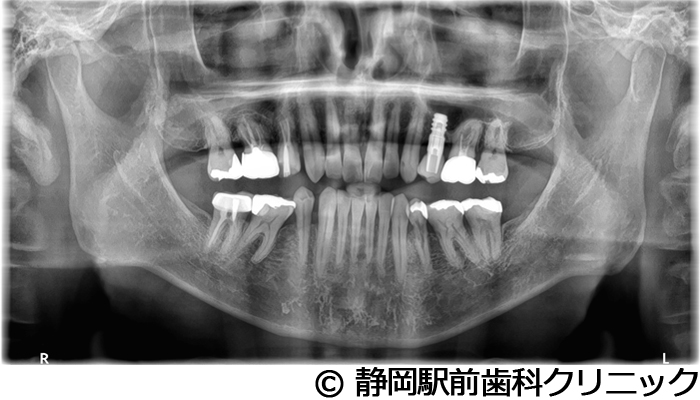

【症例4】全顎的インプラントとセラミックによる審美補綴

- 治療前

- 治療後

- 治療名

- 全顎的インプラントとセラミックによる審美補綴

- 費用

- 1,200,000円(税込)

- 期間

- 1年3ヵ月

治療内容

患者様の症状

左上ブリッジが歯根破折してしまい、他院で入れ歯を作ったが使い心地がよくないため、インプラント治療希望。

治療方法

抜歯後、骨治癒後にCTを撮影して、綿密に治療計画を立てた。上顎洞の距離やインプラント同士のバランスを熟慮し、インプラントを埋入した。全体的な噛み合わせの調整を重ねた後、人工歯を被せて咬合と見た目の回復を行った。

治療結果

入れ歯のような違和感が全くなく、力を入れてしっかり噛むことができるので、食事することが楽しくなったとご満足いただけました。見た目もセラミックの歯が入ったので、自分の歯が戻ったようだと喜んでいただきました。

※治療結果は個人差があります。

治療を行う上での注意点(リスク・副作用)

術後は、出血、腫れ、痛みなどが出る可能性があります。